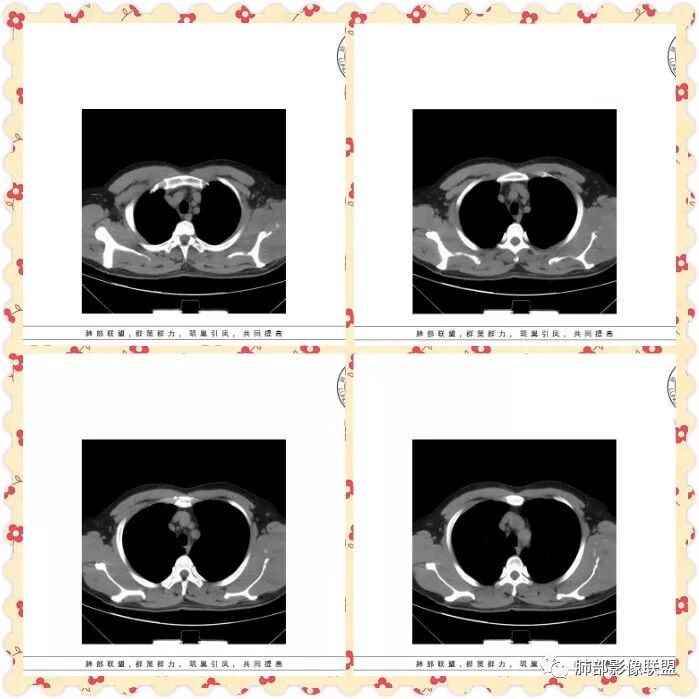

双肺多发磨玻璃影,大部分中央可见增粗血管影,部分血管边缘模糊破坏,左侧肩胛骨骨质破坏,周围巨大软组织肿块,软组织肿块内可见坏死及肿瘤骨,考虑肩胛骨骨肉瘤并双肺多发转移(点晕征)。

中年男性47岁。左侧肩胛骨骨质破坏并不规则状软组织密度影,与周围肌肉组织界限欠清。双肺内多发类圆形pggo,部分中间见血管,考虑左侧肩胛部恶性病变肺内血性转移。

管洪林:

男性,67岁,咳嗽痰中带血,左背部肿块,双肺弥漫可见磨玻璃结节,部分清晰,部分边缘模糊,部分其内可见明显点晕征,纵隔内无明显肿大淋巴结,左肩胛骨溶骨性破坏,临近明显软组织肿块,考虑左侧肩胛骨恶性肿瘤并双肺多发转移,点晕征提示血管来源。

病例分析:双肺多发磨玻璃影,部分磨玻璃影内可见点状实性结节,呈点晕征,边缘较散,模糊不清,左侧肩胛骨溶骨性骨质破坏,周围肌肉散在钙化,包绕骨质生长,综合考虑:左肩胛骨骨肉瘤伴双肺转移,其它(血管炎,多发血管瘤)

男性47岁。左侧肩胛骨骨质破坏并巨大软组织肿胀影,与周围肌肉组织界限欠清。双肺内多发圆形晕征,边缘清晰,点晕征。考虑左肩胛部恶性病变肺内血性转移,浆细胞瘤,骨肉瘤,黑色素瘤。

双肺多发磨玻璃影,部分边界清楚,部分边缘模糊,沿血管走行,其内血管明显增粗,部分磨玻璃影内可见点状实性结节,呈点晕征,左侧肩胛骨溶骨性骨质破坏,伴软组织块形成,可见少许残存骨化影,综合考虑:左肩胛骨骨肉瘤伴双肺转移,其内不出外血管炎

左侧肩胛骨溶骨性骨质破坏,伴软组织块形成,可见少许残存骨化影,双肺多发磨玻璃影,其内可见粗大血管影,部分呈点晕征,考虑:左肩胛骨骨肉瘤伴双肺转移

中年男性,咯血,双肺多发结节状、斑片状磨玻璃影,大部分中央可见增粗血管影,部分结节内见点征。左侧肩胛骨融骨性破坏并周围巨大软组织肿块,内见肿瘤骨,考虑肩胛骨骨肉瘤并双肺多发转移,均为转移瘤待排

47岁男性,咳血痰左肩背痛1月余,左肩胛骨破坏,破坏处及周边见软组织肿块,左肩胛区包块并皮肤破损,破损处无渗液、无脓不支持结核。两肺见多发磨玻璃影,沿血管走行,其内血管明显增粗,部分磨玻璃影内可见点状实性结节,呈点晕征,各磨玻璃影形态密度基本一致,提示同一来源,支气管未见明显增厚扩张——不支持气道来源。小叶间隔无增厚及纵隔未见明显肿大淋巴结——感觉淋巴瘤可能性较小。胸腹部皮肤散在红斑。整体考虑左肩胛骨恶性肿瘤并两肺转移。

quanyou:

1.双肺多发磨玻璃结节影,边界可分辨,病灶中央都可见一实性密度小结节影,注意不是钙化。这些病灶形态及密度是如此相似,宛如身着厚厚一层晕影蜉蝣深海之中,称之为“点晕征”。

注意:多发、点、厚晕